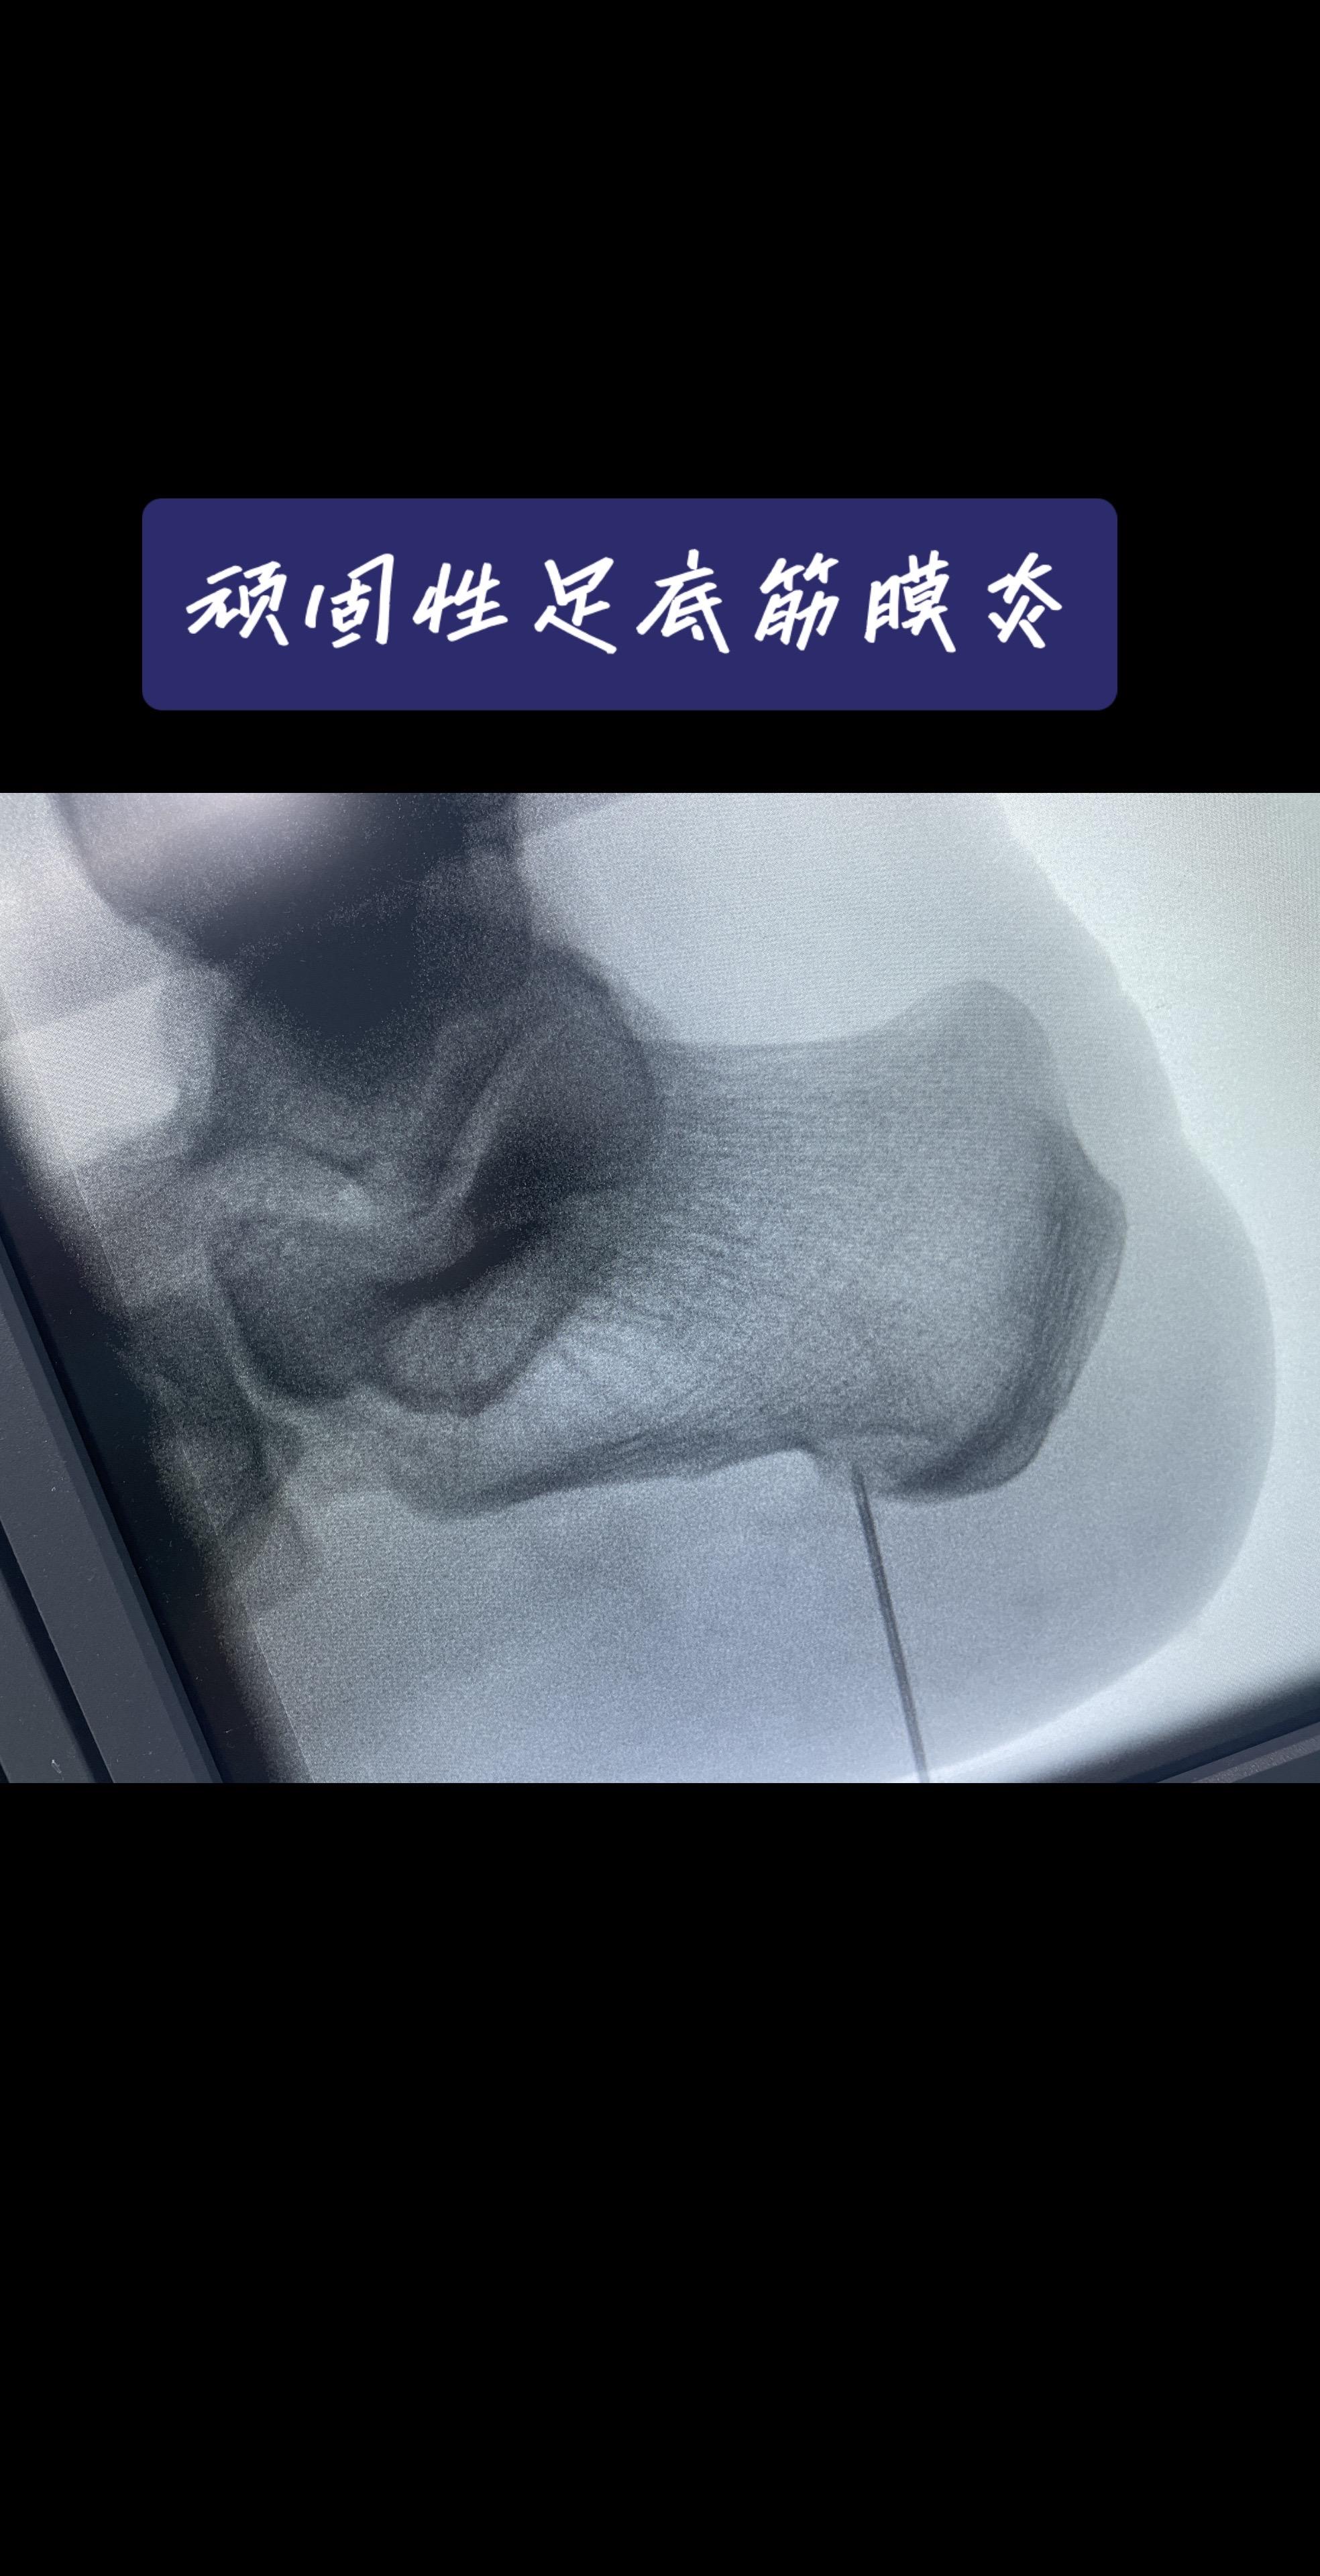

脚后跟像踩针?一走路就钻心疼?对于忍了好几年,试遍各种方法都没用的‘顽固分子’,我们怎么办?——关节镜下的‘筋膜松解术’,创伤小、恢复快,告别‘起步痛’!